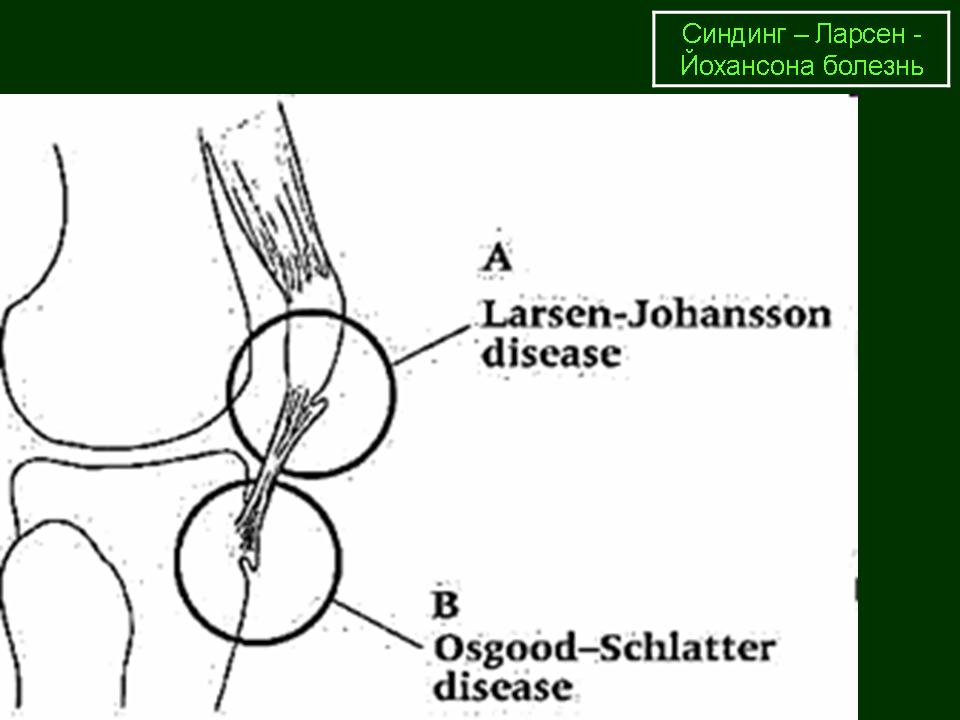

Ларсена йохансона

Ларсена йохансона 146 фото